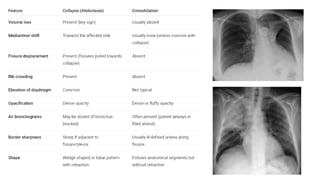

Signs of atelectasis/collapse on x ray

● Homogenous lung opacification

● Displacement of interlobar fissure towards

the atelectasis

● Mediastinal shift towards atelectasis

● Hilum and ipsilateral hemidiaphragm

elevation (peaked appearance)

● Compensatory hyperinflation

● Ribs crowding

Atelectatic opacification (collapse)

● collapse of a complete lung or part of the lung (lobe, segment or specific subsegmental area) leading to an

impaired 02 and C02 exchange and, therefore, to an intrapulmonary shunt.(Which leads to loss of air in the

alveoli)